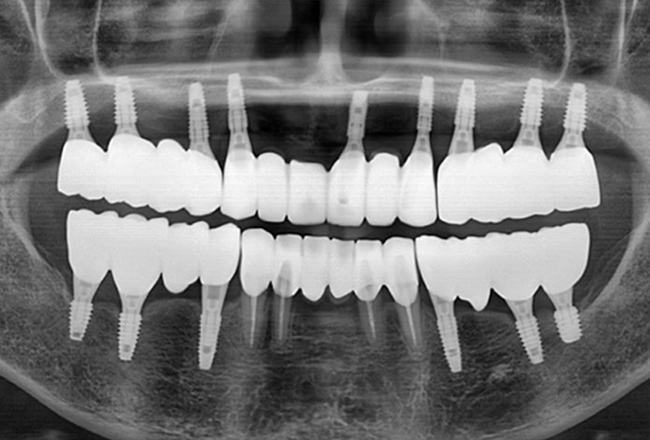

개인 치아 형태와 교합을 고려한

최종 보철물을 제작·장착합니다.

자연스러운 사용감과 기능을 확인한 뒤

치료를 마무리합니다.